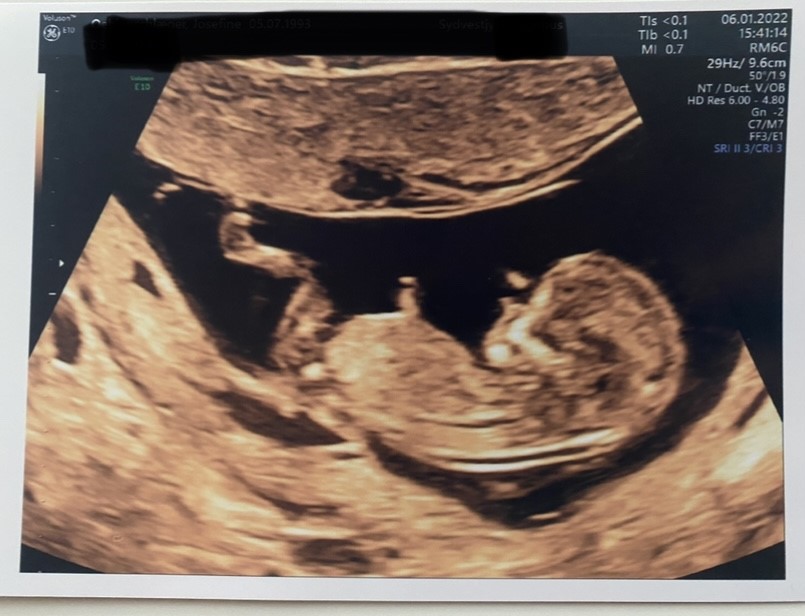

Jeg tænker det her er nubben Er det også den du kigger på?

Vedhæftede fotos (klik for at se i fuld størrelse)

Den sidder alt for lavt til at væge nubben.

Jeg har to andre billeder, men der kan man intet se.

Jeg tror heller ikke det er nubben, men omvendt tror jeg at den “tydelige Nub” er lårben, efter at have set de nye billeder.

Jeg vil derfor ikke konkludere noget - men hvis du føler dig mere forvirret, så ville jeg smide den ind i Nub Theory Queens, de vil helt sikkert kunne sige, om det ER Nub eller lårben